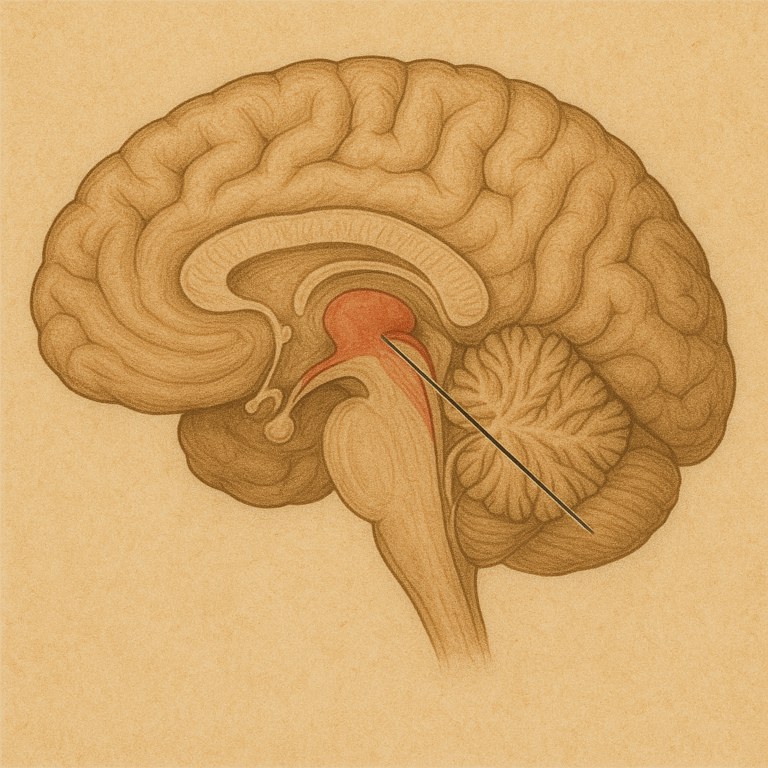

En el corazón del cerebro humano, entre los dos hemisferios, se encuentra…

En el interior del cráneo, justo en la base del cerebro y…